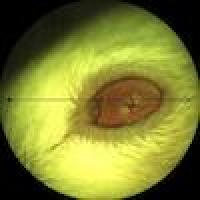

Grey scale electron microscopy image of human retinal cells.

New genetic links found to rare eye disease, opening the door to better diagnostics and potential treatments

NEI-funded research at Scripps Research Institute has turned up more than a dozen gene variants linked to MacTel, a rare eye disease. The variants are likely causing the condition to develop and worsen for a significant share of patients.